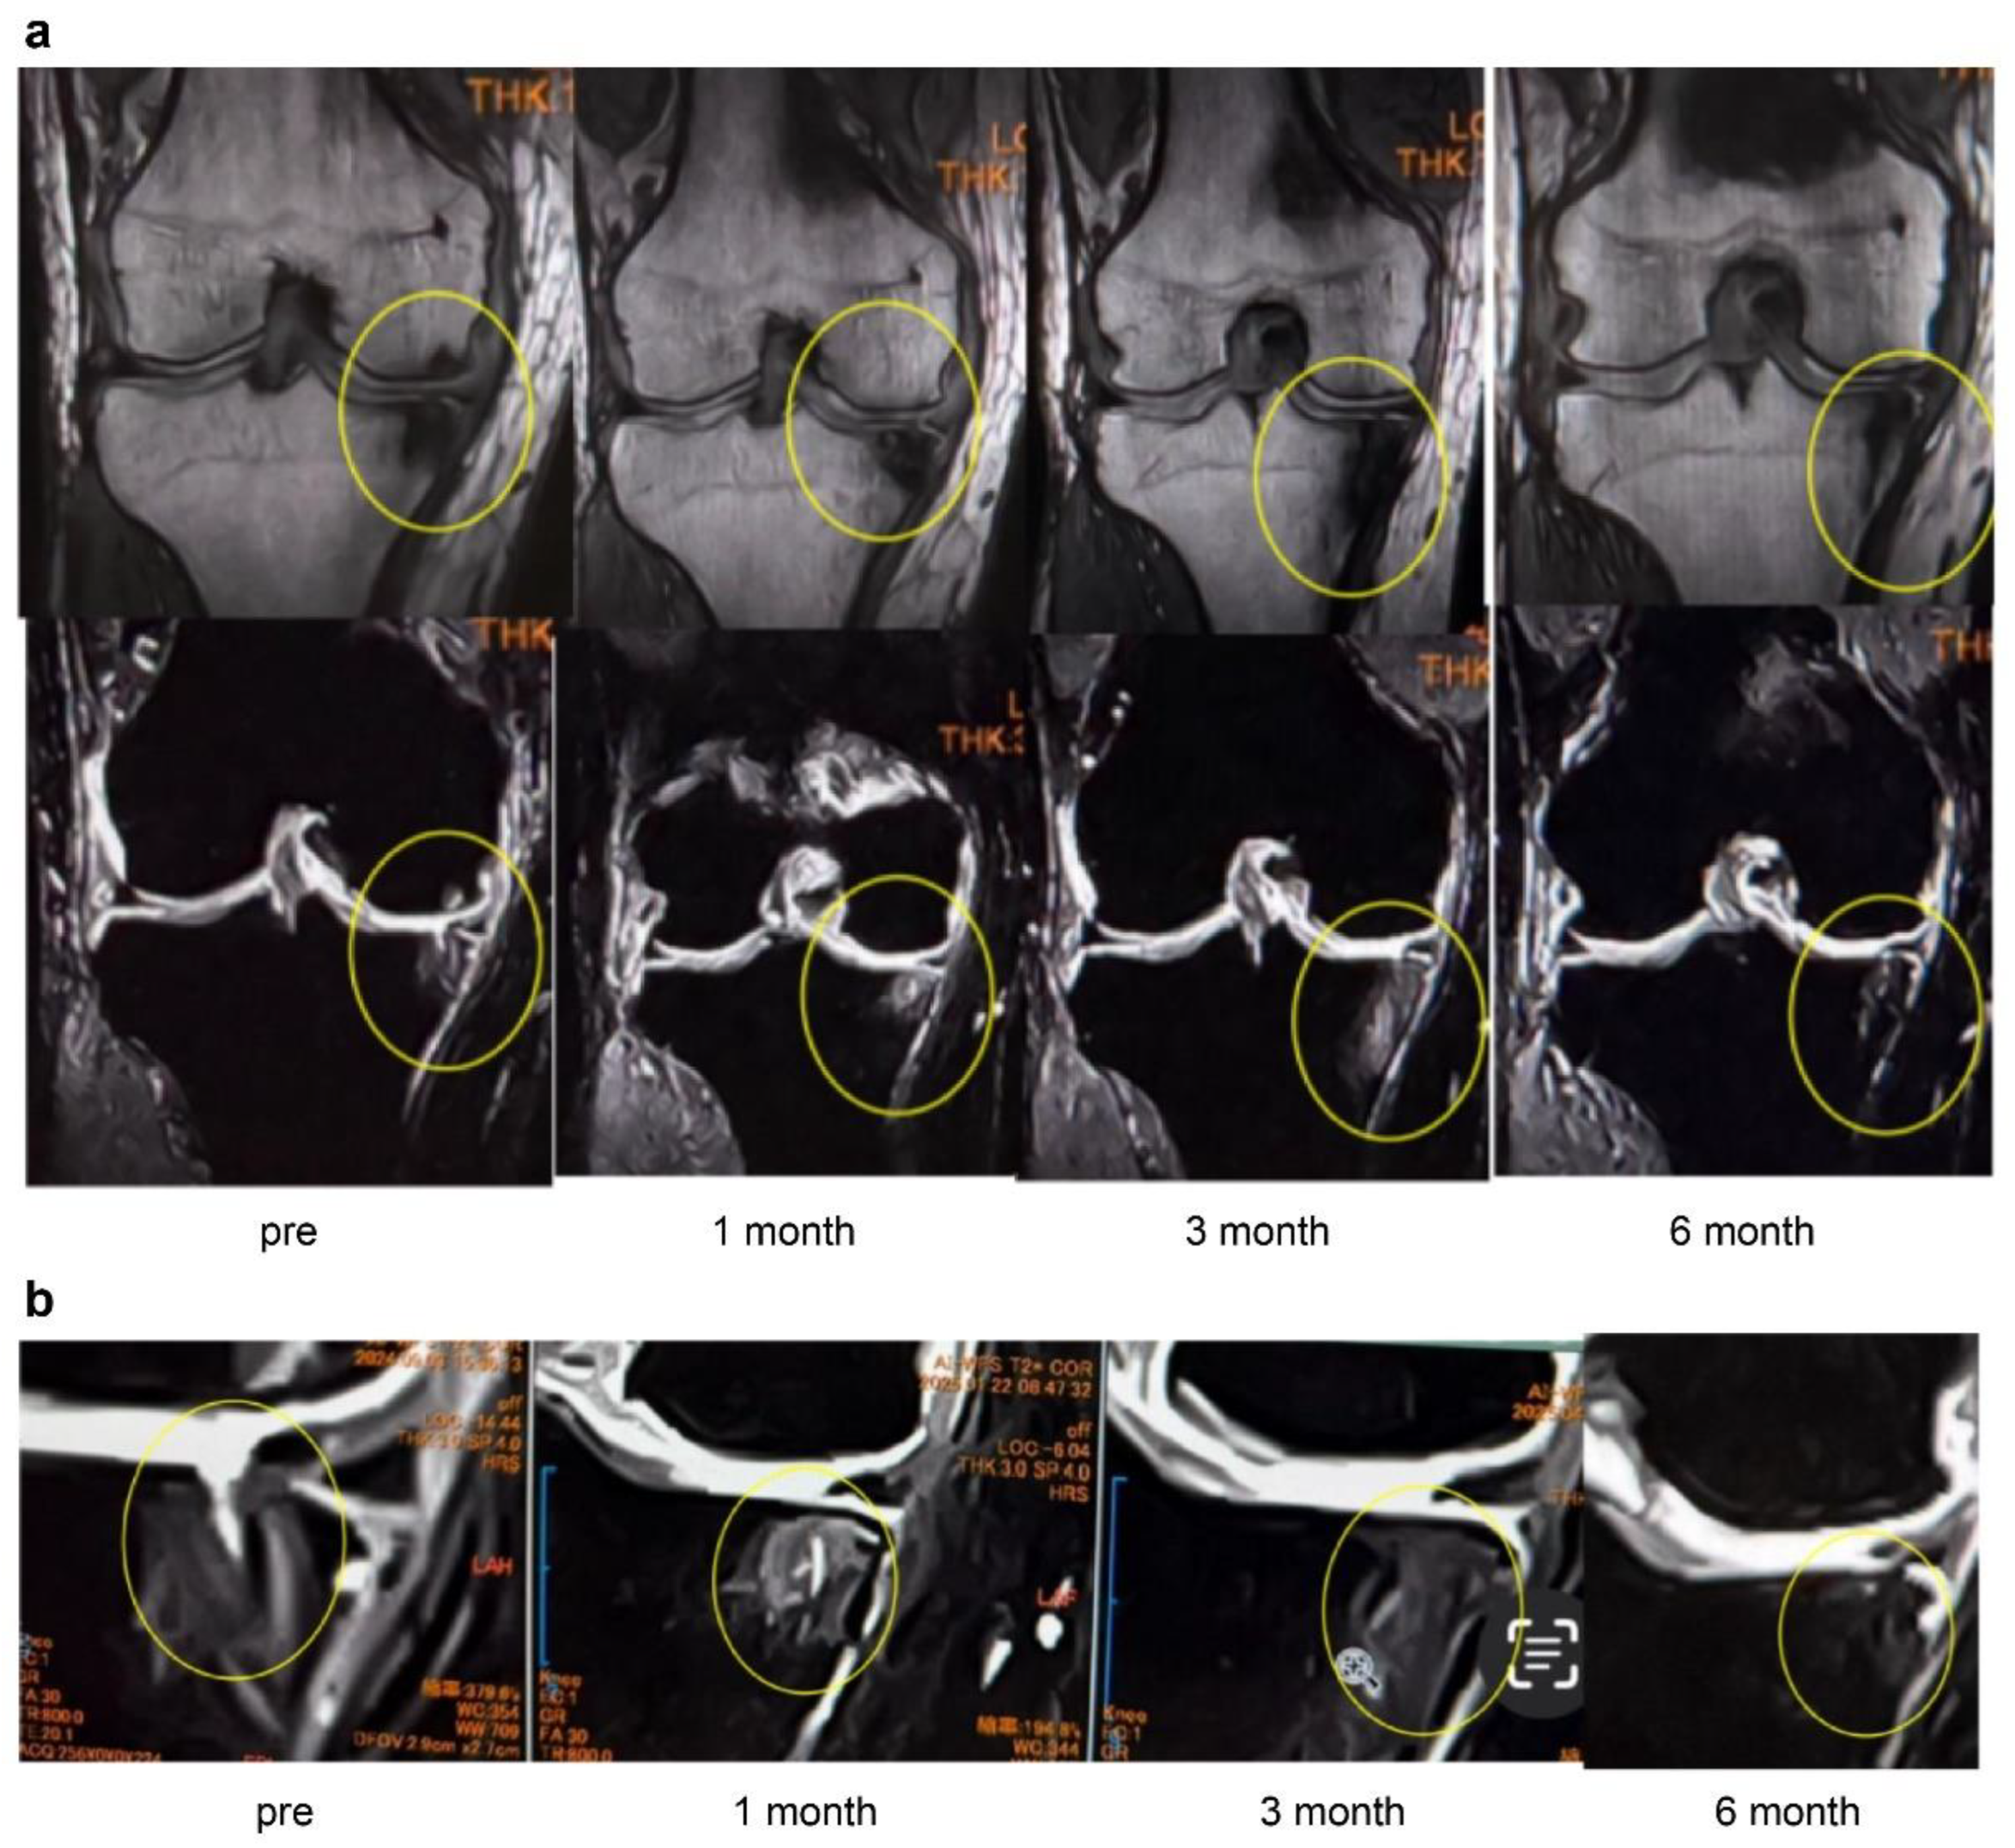

Figure 6a (case 1) shows sagittal MRI images of the knee before and 1 year after treatment with ESWT. A large BML was evident before treatment. After 13 ESWT sessions over 1 year, the BML area was markedly reduced. In addition, the previously torn SBP appeared repaired, and the thickness of the articular cartilage layer increased. These findings suggest that ESWT may exert structural improvements in the subchondral bone and the articular cartilage.

The knee in

Figure 6b (case 2) underwent a total of 50 ESWT sessions (once per month) from 2019. The left image shows the coronal MRI before treatment, and the right image shows the MRI after 5 years of therapy. While bone sclerosis was evident before treatment, the long-term images demonstrated not only improvement of sclerosis but also a clear thickening of the articular cartilage layer, as indicated by the yellow arrows. These findings suggest that long-term ESWT may contribute to cartilage protection and regeneration.

Figure 6.

(a) MRI images of the knee (Case 1). Comparison of pretreatment and 1-year follow-up MRI images shows a reduction in the BML, repair of the SBP tear, and increased cartilage thickness. BML, bone marrow lesion. (b) MRI images of the knee (Case 2). Compared with baseline, the 5-year MRI shows improvement of bone sclerosis and clear thickening of the cartilage layer (yellow arrows), suggesting long-term cartilage protection and regeneration.